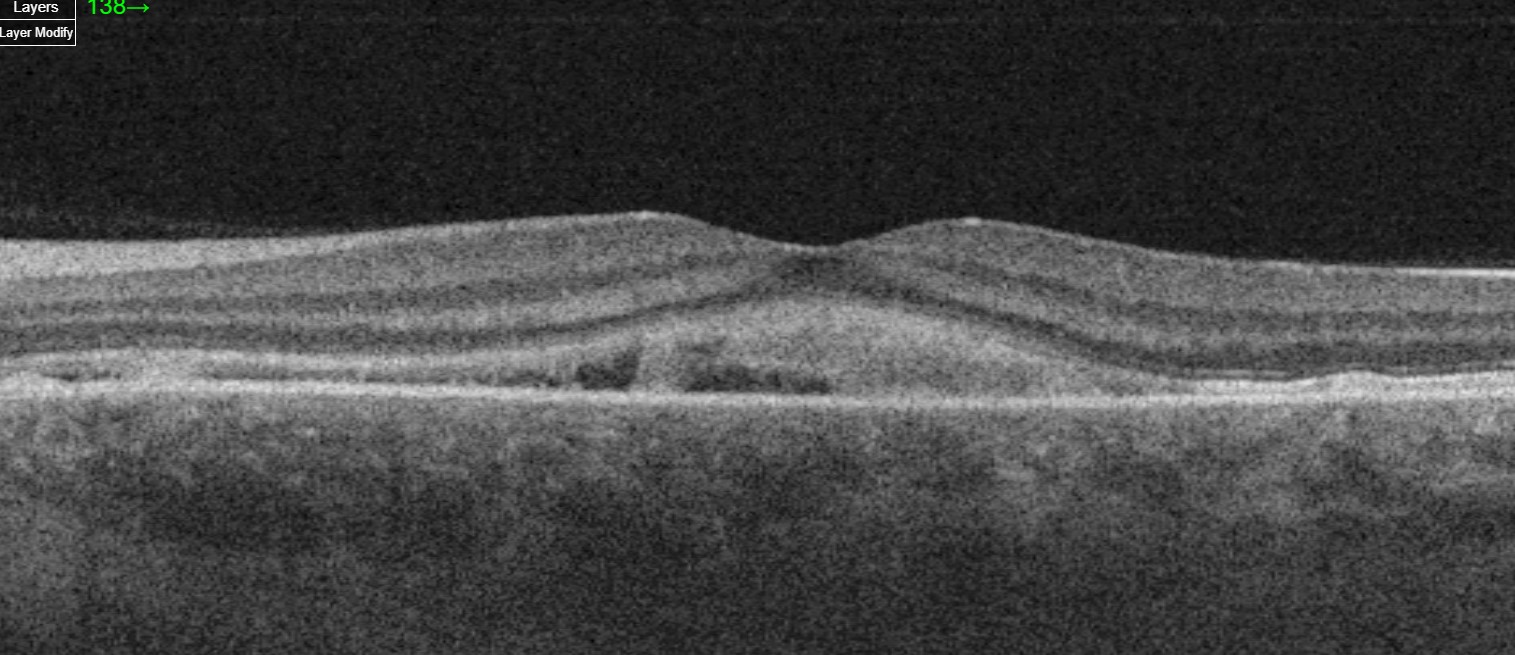

- Fundoscopy and OCT Findings:

- Macular Subretinal Fluid: Fundoscopy and OCT imaging often reveal significant subretinal fluid accumulation under the macula, impairing vision. This fluid results from leakage due to damaged blood vessels in the retina or choroid.

- Subretinal Deposits or Fibrin: OCT can detect subretinal deposits or fibrin, indicating severe inflammation or exudation caused by the breakdown of the blood-retina barrier. These changes usually resolve rapidly as systemic hypertension improves, though they signify substantial vascular compromise.

- RPE Mottling: Irregular pigmentation or mottling of the retinal pigment epithelium (RPE) may persist even after the acute fluid and deposits have resolved, reflecting chronic damage to the RPE cells.

- Fluorescein Angiography (FA): This imaging technique can show delayed perfusion in segments of the choroid and multiple pinpoint areas of dye leakage through the RPE, particularly around subretinal yellow-white patches. Early in the disease course, FA may reveal delayed choriocapillaris perfusion due to ischemia, while later stages exhibit a multifocal reticular staining pattern over areas of RPE damage.